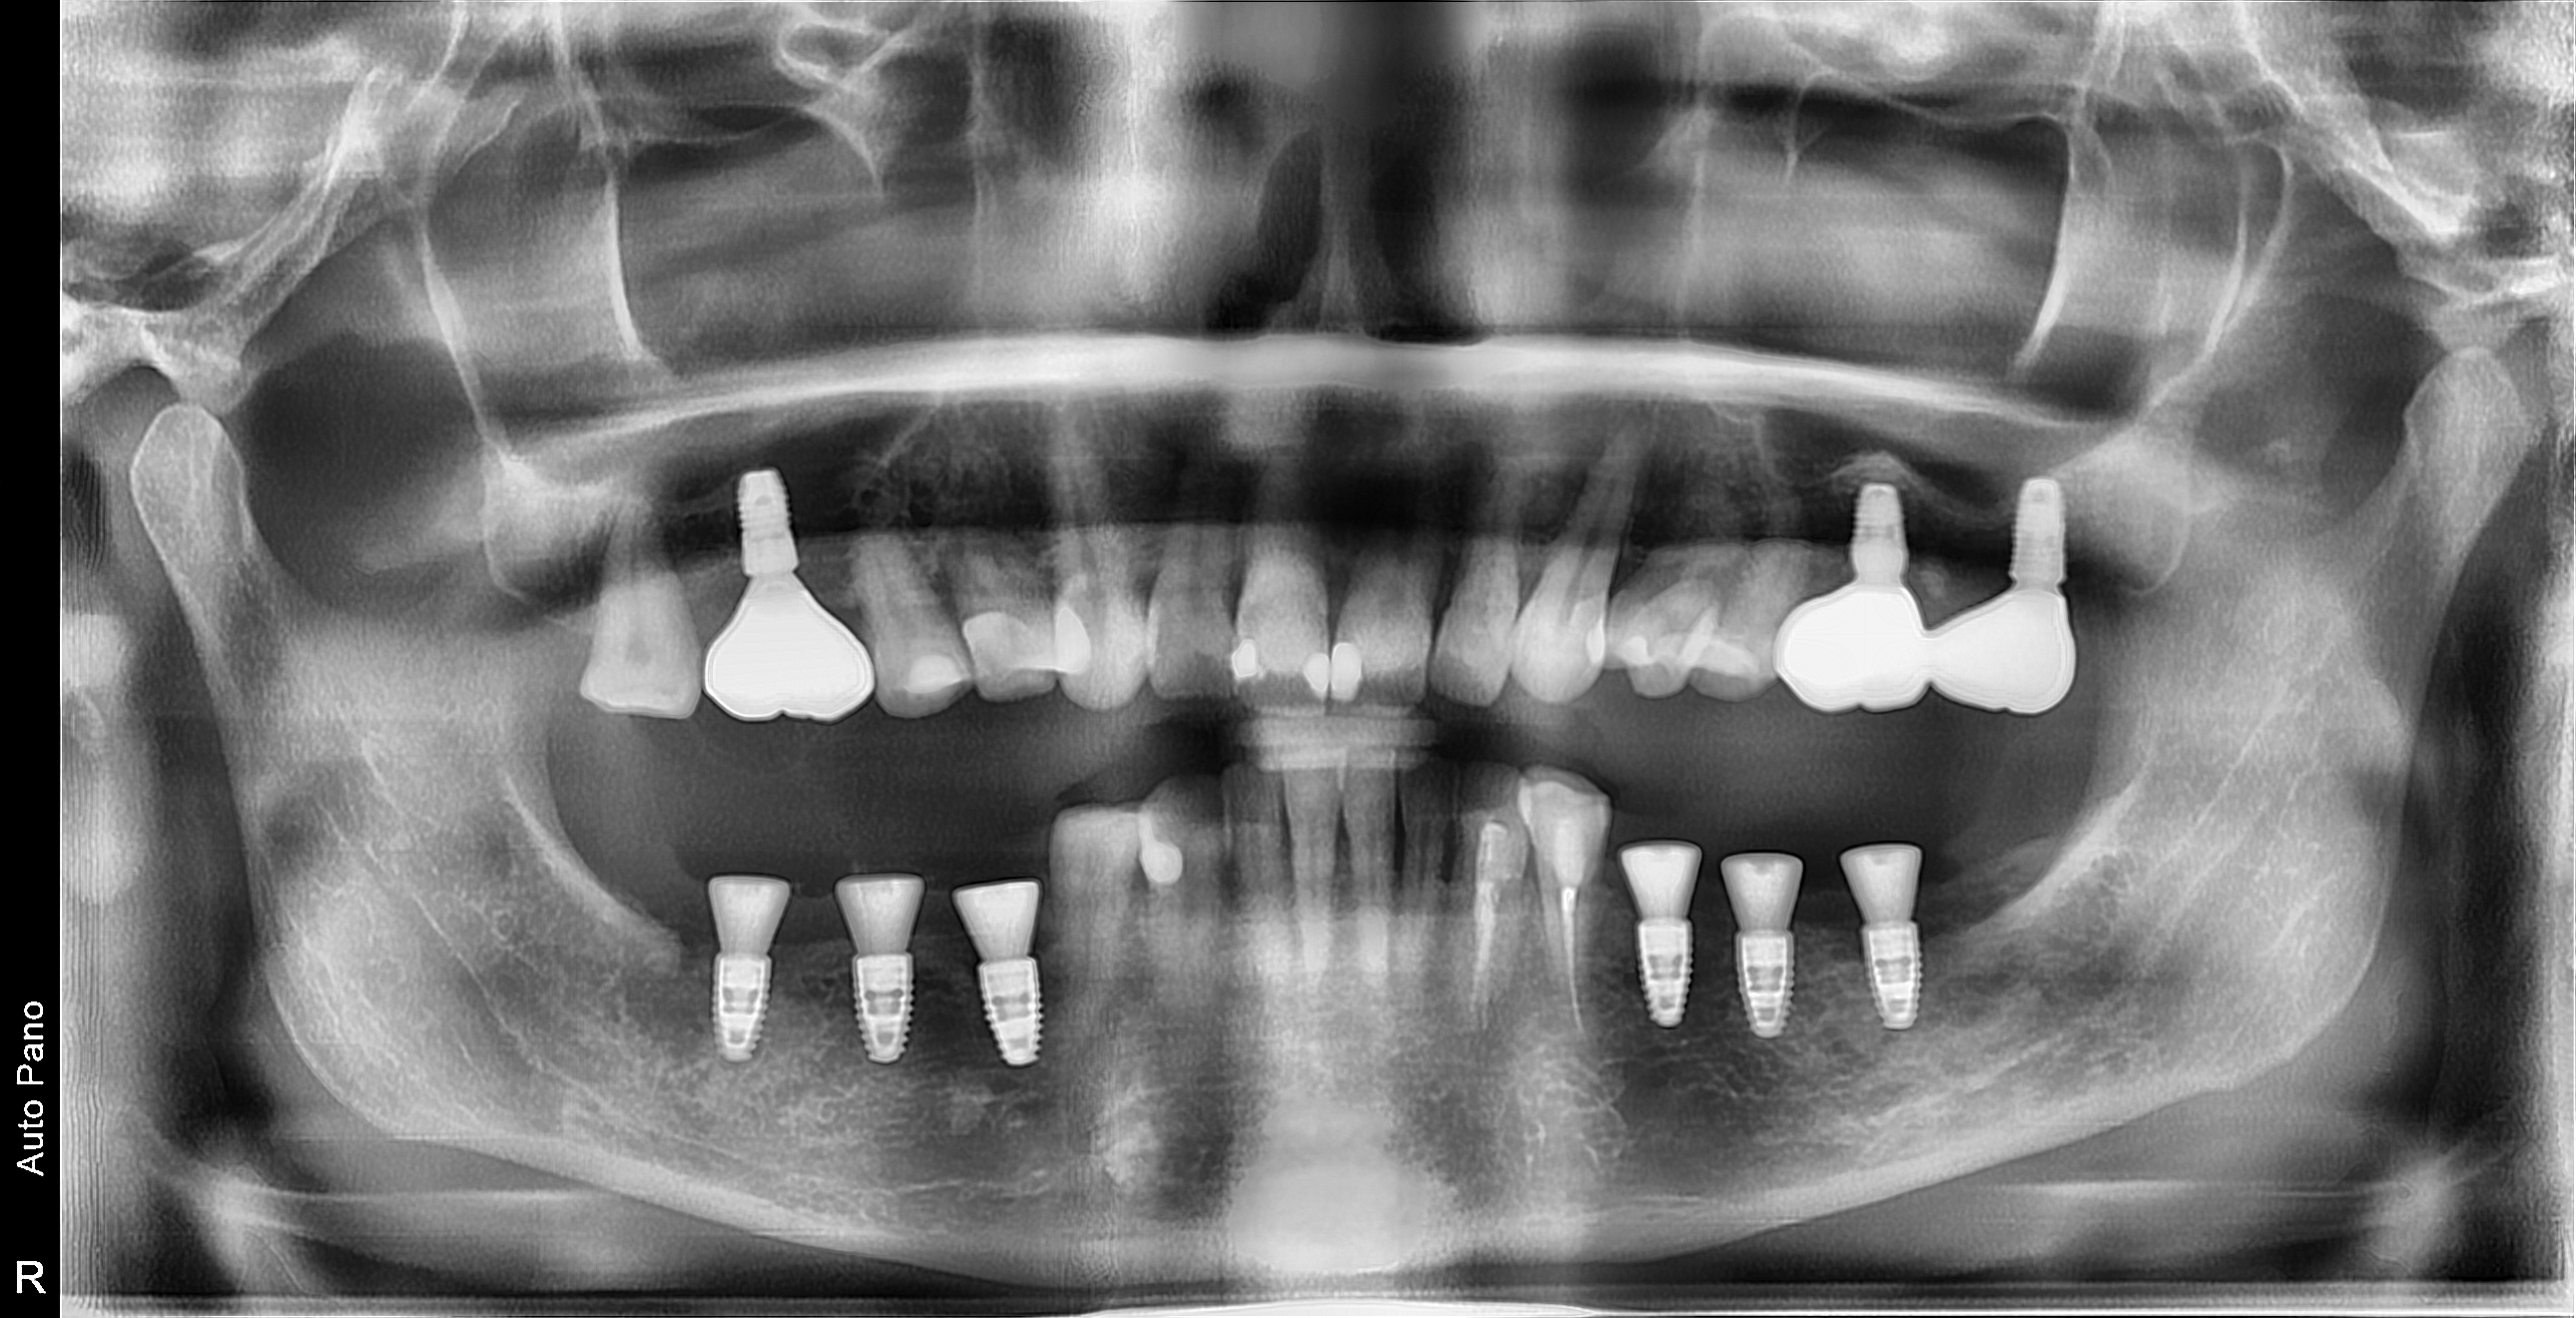

- Планирование и функциональна реабилитация пациентов с полным отсутствием зубов с применением дентальных имплантатов.

- Дентальная имплантация в полном объеме в том числе при сопутствующей патологии. (одноэтапная и двухэтапная методики; непосредственная и отсроченная нагрузки). Использование хирургических шаблонов.

- Открытый и закрытый синус-лифтинг с одномоментной и отсроченной дентальной имплантацией.